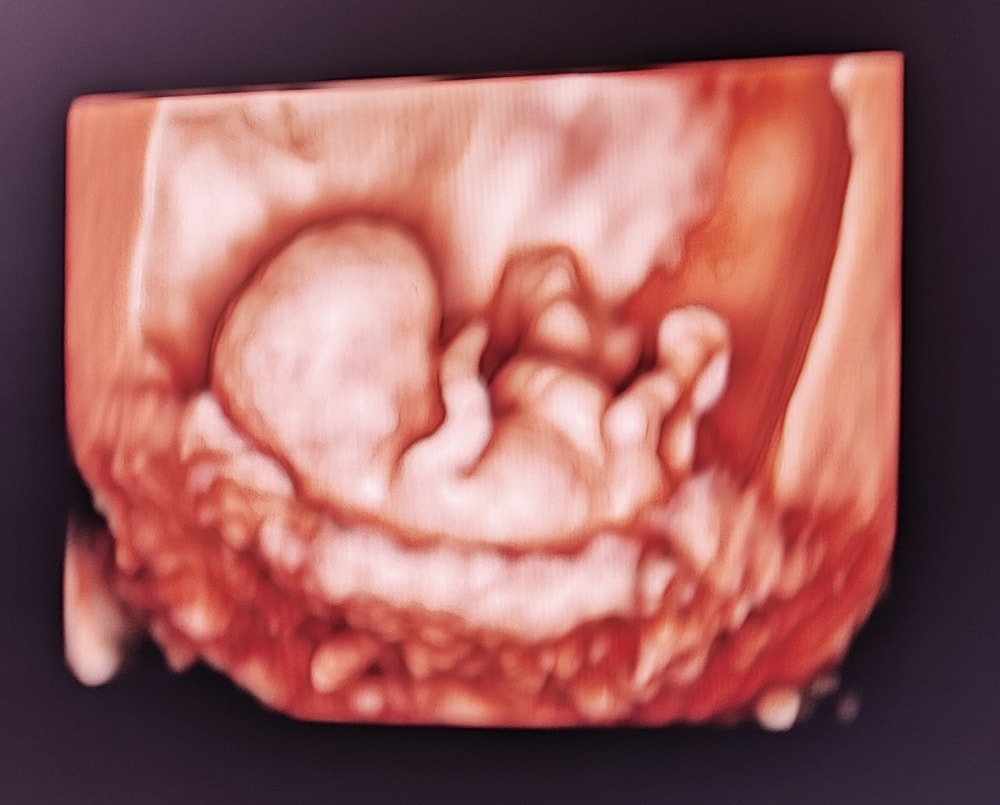

4 УЗИ перед НИПТ (15.06.25):

По менструации 9+5 / По овуляции 10 / По УЗИ 10+3

КТР 3,5 см

Сердцебиение 172 уд/мин

Сделали красивые фоточки, малышок уже прям человечек совсем, это первое УЗИ на которое ходил муж, до этого только на видео ему показывала. Есть пупочная грыжа, но вроде не большая, сказали это в пределах нормы для этого срока, к скринингу должно пройти скорее всего ♥️